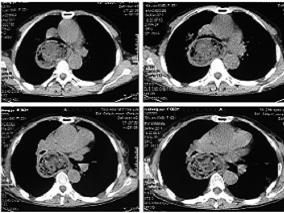

1小时条评论一、病史摘要 患者,女性,63岁,因咳嗽、喘息11天于2011年3月2日入院。患者2月20日晚因反酸、呕吐后出现咳嗽、喘息、气促,不能平卧,伴全身大汗,持续约1小时后自行缓解。数日来喘息症状反复发作,多在活动或进食后诱发或加重。2月24日至当地医院诊断为喘息性支气...